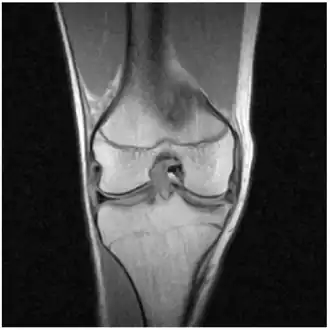

-

MRI of right knee revealing intra-articular and bucket-handle medial meniscus tear with the displaced fragment located in the intercondylar notch. -

X-ray images (normally during weightbearing) can be obtained to rule out other conditions or to see if the patient also has osteoarthritis. The menisci themselves cannot be visualised with plain radiographs. If the diagnosis is not clear from the history and examination, the menisci can be imaged with magnetic resonance imaging (an MRI scan). This technique has replaced previous arthrography, which involved injecting contrast medium into the joint space. In straightforward cases, knee arthroscopy allows quick diagnosis and simultaneous treatment. Recent clinical data shows that MRI and clinical testing are comparable in sensitivity and specificity when looking for a meniscal tear.